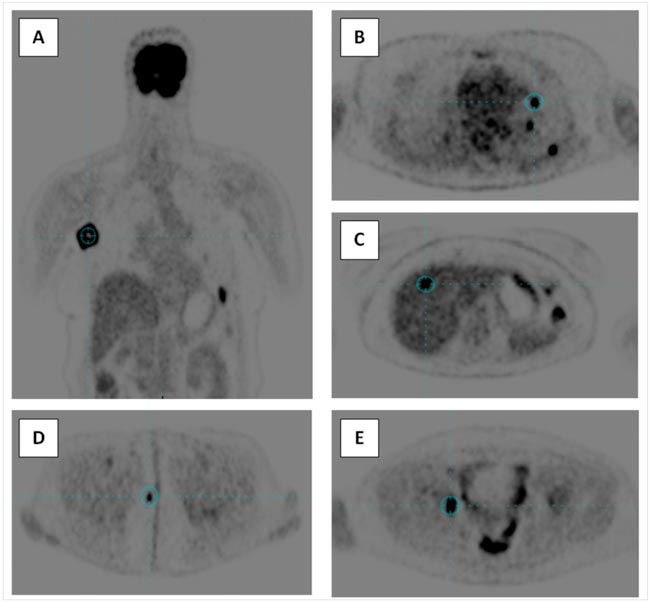

А ВОТ БЫЛ У МЕНЯ ОДИН СЛУЧАЙ , ИЛИ «ОХОТНИЧЬИ ЗАПИСКИ» ОНКОЛОГОВ... / ПРОЛГОЛИМАБ В ЛЕЧЕНИИ МЕТАСТАТИЧЕСКОЙ BRAF-ОТРИЦАТЕЛЬНОЙ МЕЛАНОМЫ КОЖИ: ЧЕРЕЗ ПСЕВДОПРОГРЕССИЮ К ПОЛНОМУ ОТВЕТУ

Пролголимаб – рекомбинантное моноклональное антитело, специфически связывающее рецептор программируемой клеточной смерти PD-1 и блокирующее его взаимодействие с лигандами PD-L1 и PD-L2. Пролголимаб одобрен в России для...

В связи с развитием молекулярногенетической диагностики при злокачественных новообразованиях наблюдается устойчивая тенденция к выбору персонализированного подхода в лечении. За последние 10 лет в таргетной терапии (ТТ)...